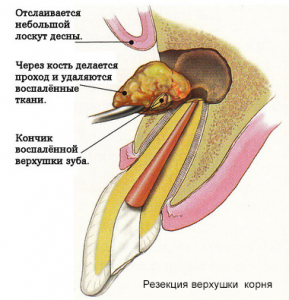

Если медикаментозное лечение результатов не даёт, и киста не рассасывается, прибегают к хирургическому вмешательству – производят резекцию верхушки корня зуба, цистотомию и цистэктомию (различные способы удаления кисты).